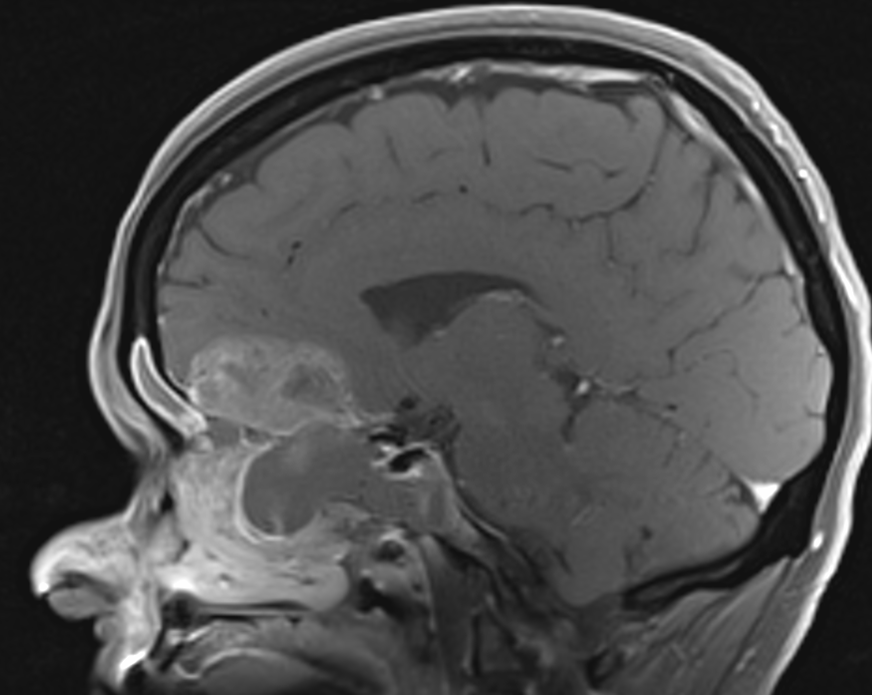

Dona de 59 anys, fumadora de 15-20 cigarretes/dia fins fa 10 anys, sense altres hàbits tòxics destacables, amb antecedents patològics de Diabetes Mellitus tipus I que tracta amb insulina, Hipertensió arterial, i dislipèmia. Consulta per cuadre progressiu desde fa 5-6 mesos d'anosmia, cefalees hemicraneals esquerres, hipoestesia d'hemicara esquerra, epistaxis esquerres que es fan diàries, visió borrosa amb diplòpia, i tumefacció cervical esquerra. A l'exploració física s'observa exoftalmos esquerre i adenopaties laterocervicals esquerres indurades, i a l'estudi ORL s'observa lesió polipoidea eritematosa a fossa nasal provinent de meat superior esquerre. Es realitzen diverses proves de Diagnòstic per la imatge, i es realitzen simultàniament punció aspirativa i biòpsia de la lesió a fossa nasal. S'adjunten imatges de la RNM cranial, i de punció aspirativa.